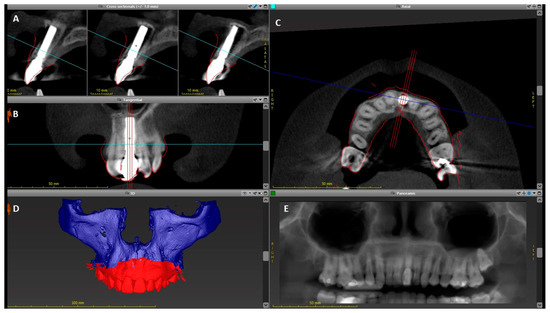

2. Materials and Methods

| Implant Shoulder | 1 mm | 2 mm | 4 mm | Mean Thickness | |

|---|---|---|---|---|---|

| Bone | 1.7 | 1.5 | 1.5 | 1.1 | 1.45 |

| Soft tissue | 1.1 | 1.1 | 1.2 | 1.8 | 1.3 |

| Combined tissue thickness | 2.8 | 2.6 | 2.7 | 2.9 | 2.75 |